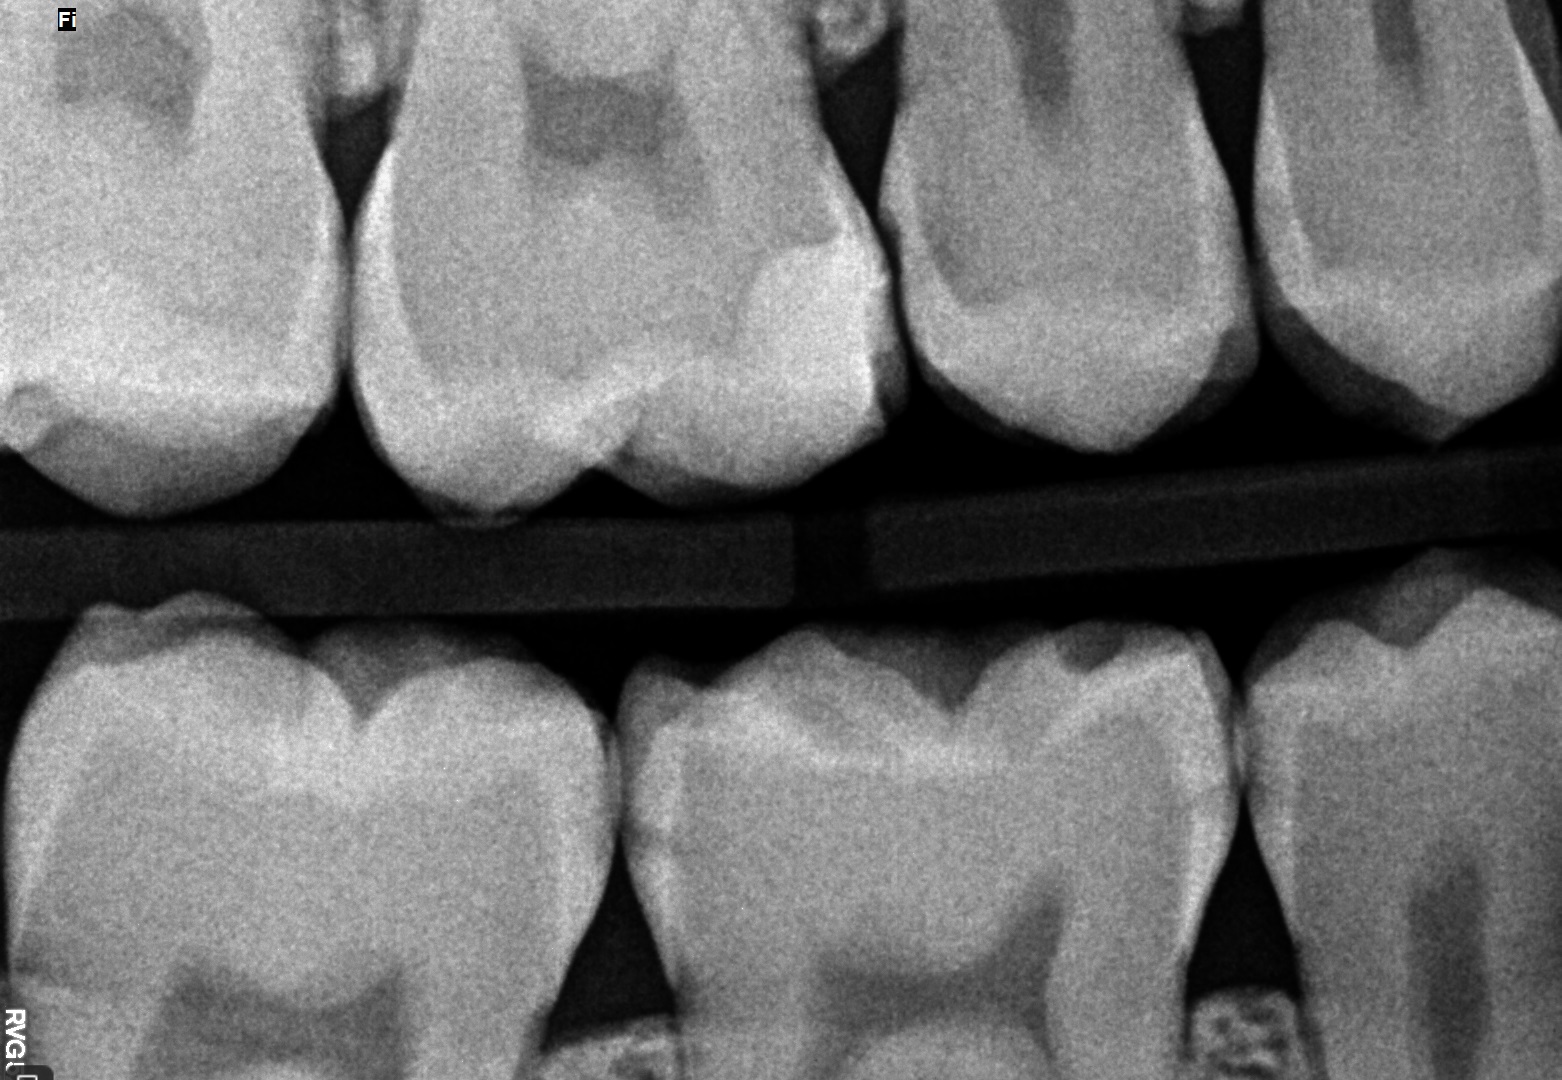

W celu oceny rozległości ubytków klasy II, diagnostykę poszerzono o zdjęcia zgryzowo‑skrzydłowe (ryc. 5 i 6). W zębie 15 dystalnie zdiagnozowano ubytek głębokości D2, mezjalnie E2, w zębie 14 dystalnie D1.

Ryc. 5. Zdjęcie skrzydłowo‑zgryzowe – strona prawa.